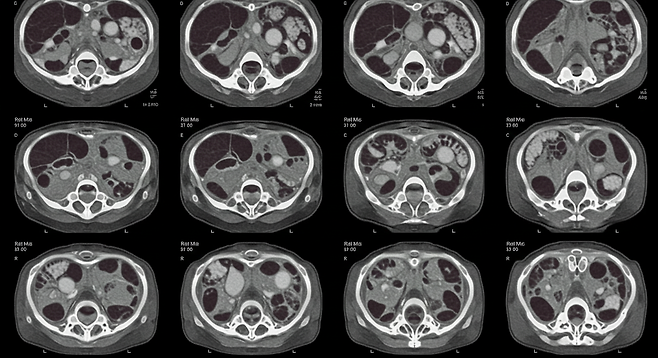

상복부 초음파나 CT 검사로 2cm 미만 종양을 찾아내는 것이 생존율을 결정합니다.